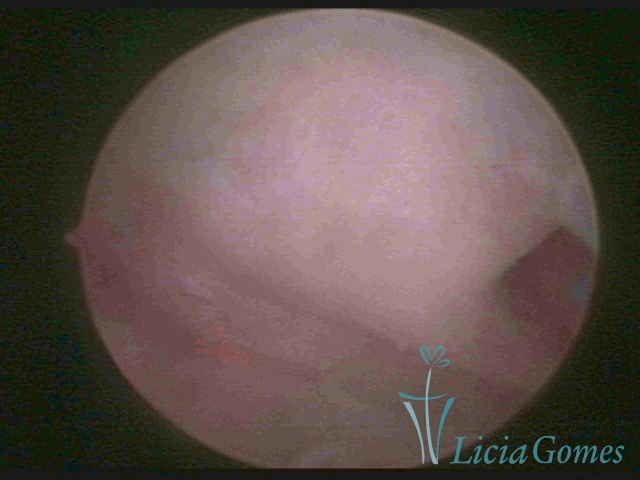

Unicornuate uterus

It presents a tubular cavity with an impaired intracavitary space, resembling the shape of a banana, whose the narrowest edge contains the tubal ostium. The endometrium is compatible with the menstrual cycle and the cervical canal is normal, in structure and trophism.